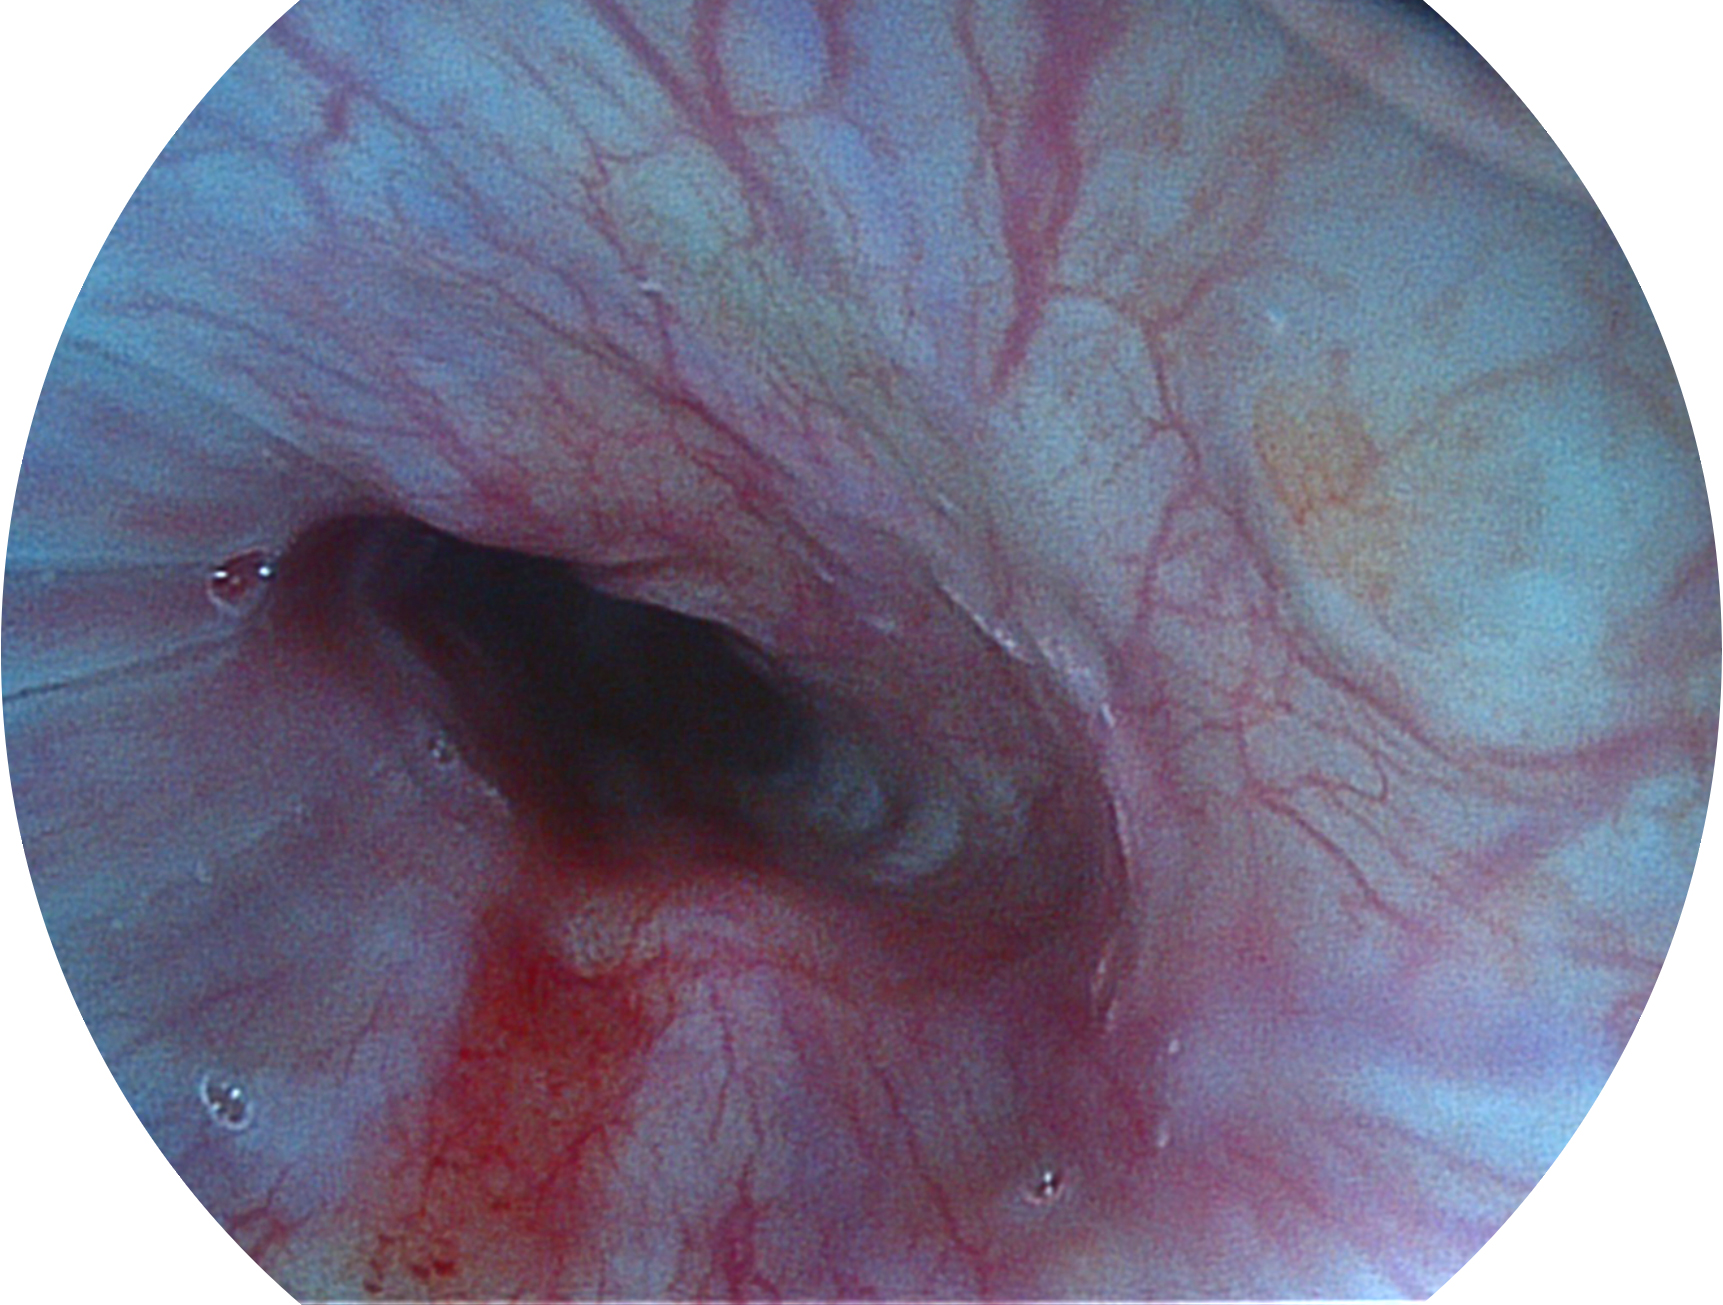

• 白光图像 SFI图像